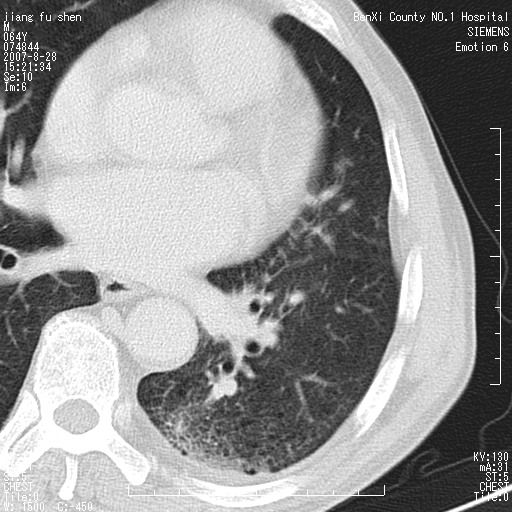

男、64、咳嗽、发烧一周、左肺呼吸音稍弱。既往肺结核,右手结核。

本次扫描患者未带原片,左肺下叶发现病灶。左肺上叶空洞,5组淋巴结肿大,1cm左右。

追问病史三月份ct扫描左肺上叶空洞,医大诊断肺结核。

支持中心型肺癌,不除外内膜结核。